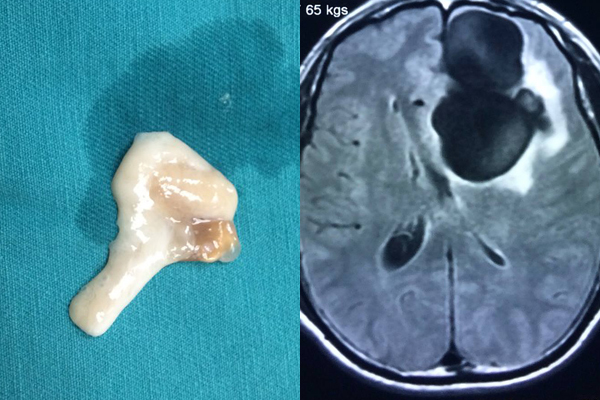

Mê tiết canh, nam thanh niên bị sán làm tổ to trong não

- Sau khi ăn tiết canh, từ cơn đau đầu, choáng váng, nam thanh niên bất ngờ chuyển co giật rồi hôn mê.